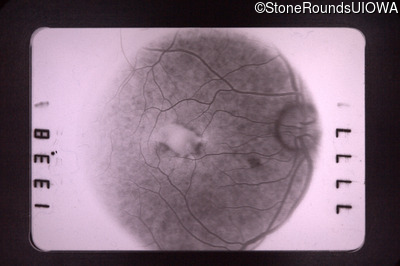

Fluorescein Angiography - Right - 20/70 -1 cc

Exemplar